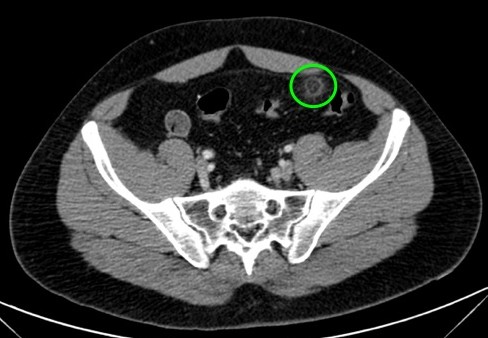

Se sospecha diverticulitis, se realiza TAC de abdomen:

Al igual que el caso anterior, nos encontramos nuevamente ante una apendagitis. Esta vez la sospecha era por diverticulitis, la anterior creíamos enfrentarnos a una apendicitis probablemente.

TAC: Imagen oval con aumento de la atenuación central, inferior a 5 cm de diámetro, contigüa al colon, con afectación de la grasa periférica. El aumento de la atenuación central es un signo de trombosis venosa muy útil para el diagnóstico, pero su ausencia no excluye en diagnóstico de apendagitis. Otros hallazgos, como aumento de la pared colónica o formación de abscesos son raros. Aunque los síntomas remiten en dos semanas, los cambios en la TAC pueden prolongarse más tiempo (pueden mantenerse, disminuir o quedar una atenuación residual), aunque en 6 mese suele haber remitido completamente. En Ecografía suele observarse en el área de máxima sensibilidad al dolor, una masa hiperecogénica, inferior a 5 cm, no compresible, adyacente al colon y sin señal Doppler.